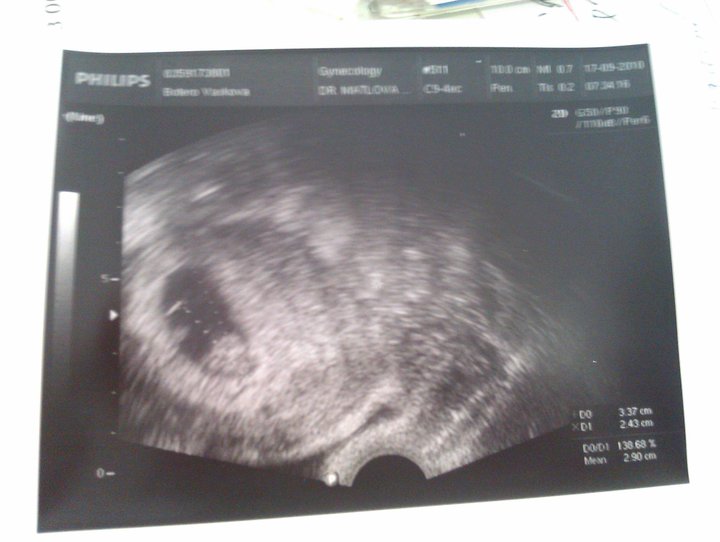

And here is the proof 🙂

Is there Hanicka or Carlito? Who can say?

We love you and we are waiting for you…………so far our Baby Bean :0)